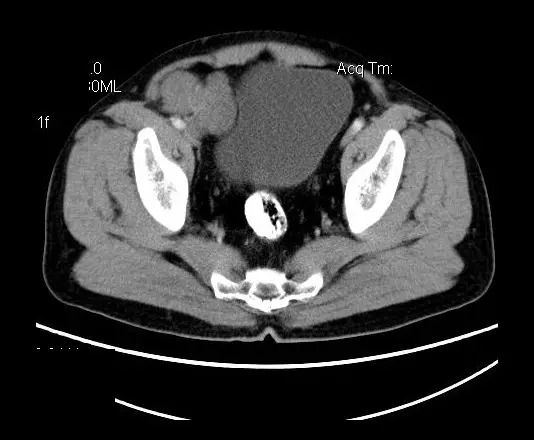

【影像表现】

盆腔右前侧及邻近腹股沟区可见多发大小不等的聚集生长的结节影,病灶呈软组织密度,边缘尚规整,分界尚清,增强扫描可见不均匀强化。膀胱局部受压,盆腔未见明显肿大淋巴结影。

“盆腔”多发性神经鞘瘤

平扫影像表现:Antoni A区较多病灶,在CT上呈等或略高密度影,T1WI等信号、T2WI略高信号,AntoniB区较多病灶,CT多为水样低密度、T1WI低信号、T2WI明显高信号。

增强影像表现:神经鞘膜肿瘤增强后,由于Antoni A区与B区以不同比例混合而强化不一,呈不均匀斑片状,条状强化。Antoni A 区富血供,中等或明显强化,Antoni B区乏血供,强化多不明显。